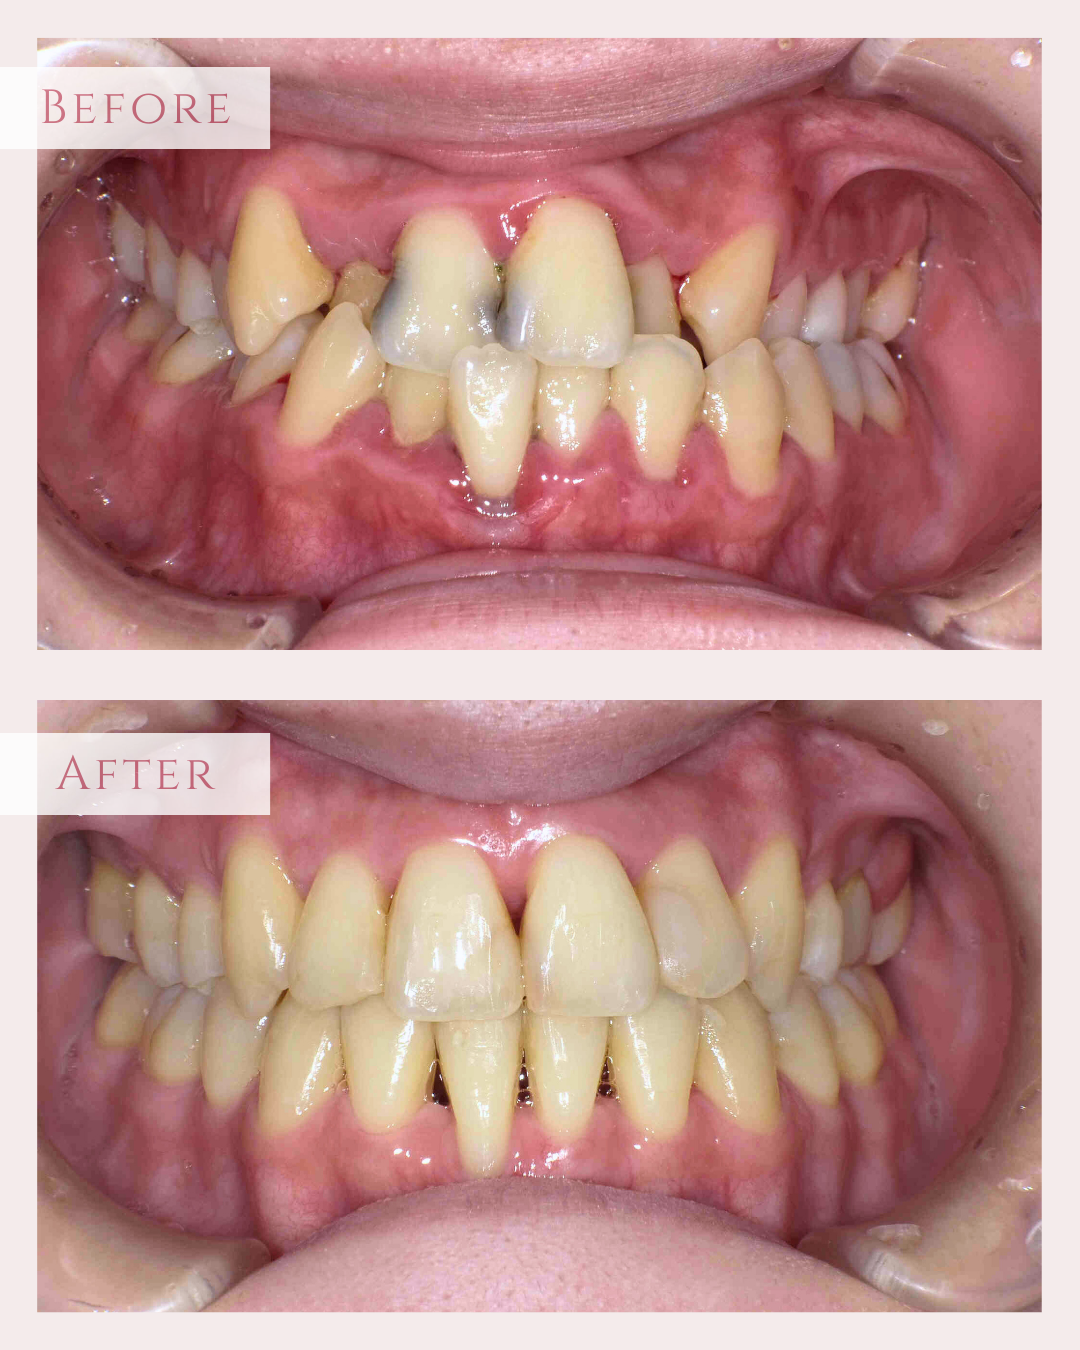

• 治療前

治療後

元々咬む筋力や食いしばり・歯ぎしりが非常に強く、『フレアーアウト』(前歯の歯並びが前方に放射状に倒れていく現象)によって「出っ歯」や「すきっ歯」の状態になっていました。

歯並びの問題だけでなく、顔つきが変わったり、前歯で食べ物を噛むことが難しくなるなど、機能面にも支障をきたします。

今回はご希望のマウスピース矯正で、食いしばりや歯ぎしりによる歯の破折やすり減りを予防しながら、歯と歯の隙間が広がって傾斜した前歯を元の位置に戻しました。

ホワイトニングも同時進行で施術し、白く輝く歯になりました。

元々入っていた臼歯のブリッジは治療せず、そのままの位置で矯正を行うことを希望されたため、正中(上顎と下顎の中心線)を合わせることは難しいですが、美しい歯列と口元へ仕上がりました!